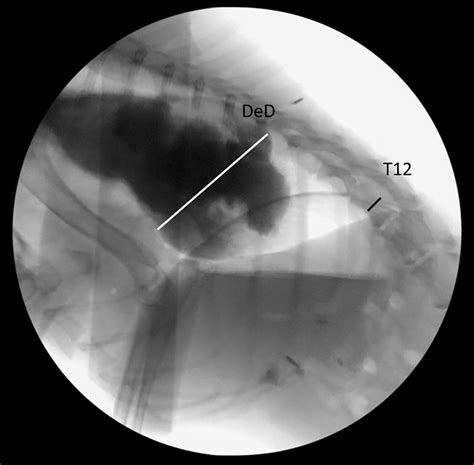

The Videofluoroscopic Swallow Study (VFSS), also known as a modified barium swallow, is a diagnostic procedure that uses fluoroscopy and a barium-based contrast material to visualize the swallowing process. This study helps identify the specific phase of swallowing that is impaired, whether it is the oral, pharyngeal, or esophageal phase.

1. The patient is positioned in front of a fluoroscopy machine, which emits X-rays to create real-time images of the swallowing process.